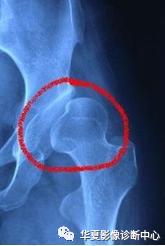

X线:

股骨头近端骨化中心出现(4~6月龄),即可推荐。

平片常规摄双髋正位和蛙式位片,典型表现包括:

①股骨头向外上移位;

②股骨头骨骺发育小、不规整,或出现延迟;

③髋臼顶发育不良呈斜坡状,髋臼角加大,可达50° - 60°;

④患侧股骨发育较细小,股骨颈短缩。

⑤骨盆:单侧脱位骨盆倾斜,双侧脱位骨盆较垂直、前倾。

⑥包绕股骨头的半弧形关节囊其上缘与髋臼顶不相接,其上方可见三角形透亮区。

上图:骨盆正位